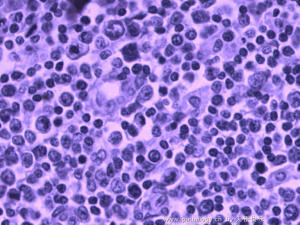

外陰癤病細胞結構圖(二)特點是病變不易局限化,迅速擴散,與正常組織無明顯界限。表淺的急性蜂窩組織炎局部明顯紅腫、劇痛,並向四周擴大,病變中央常因缺血而壞死。深部的蜂窩織炎,局部紅腫不明顯,只有局部水腫和深部壓痛,疼痛較輕,但病情較嚴重,有高熱、寒戰、頭痛、全身乏力、白細胞計數升高,壓迫局部,有捻發音。蜂窩組織和筋膜有壞死,以後可有進行性皮膚壞死,膿液惡臭。

外陰癤病細胞結構圖區別:外陰毛囊炎與外陰癤病的區別:外陰毛囊炎與外陰癤病均表現為外陰部疼痛,嚴重時都可有發冷、發熱,檢查外陰病變部均有紅腫及觸痛。其區別在於外陰毛囊炎病變較表淺且圍繞著毛囊部,毛囊口周圍皮膚發紅,有一膿皰,中心部有一根毛髮穿出;外陰癤病實際上是毛囊炎向深部發展而成的急性膿腫,因此疼痛加重,癤腫處皮膚呈圓形突起,表麵皮膚緊張,突起處初為一硬結,當局部出現膿腫時,表面變薄,呈黃白色,有波動感。